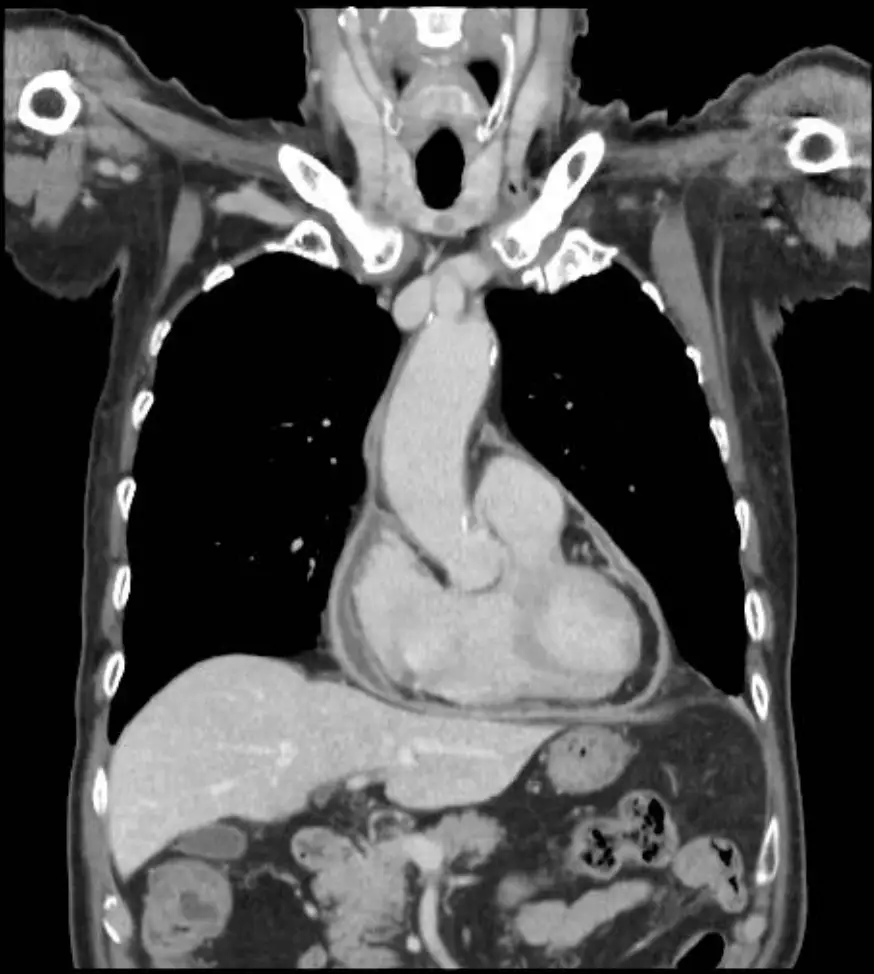

- 胸部電腦斷層(axial 與 coronal):可見心室壁弧形增厚,心包膜不增厚亦無鈣化;下腔靜脈與肝靜脈擴張,進一步支持系統靜脈鬱積。

整體影像組合指向 restrictive cardiomyopathy 而非 constrictive pericarditis或左心衰竭。